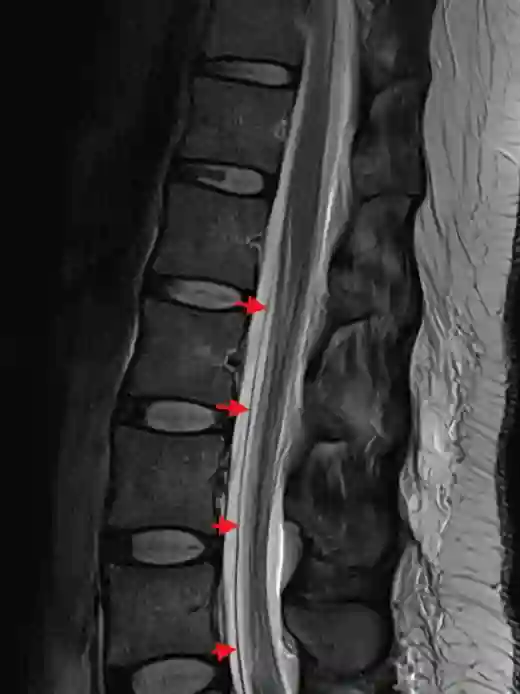

SLEC T2 MRI

Darstellung einer duralen Doppelkontur (SLEC), markiert mit roten Pfeilen in einem sagittalen T2 MRI Bild der thorakalen Wirbelsäule.